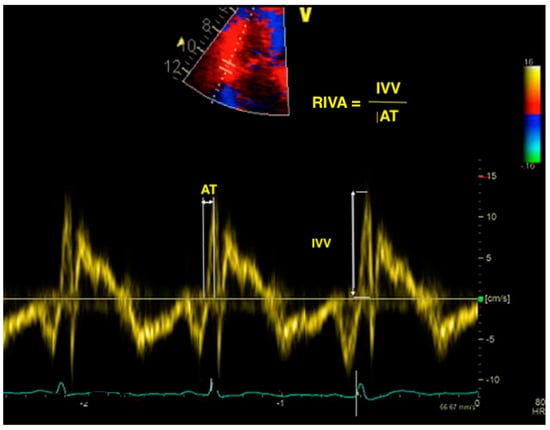

7. Right Ventricular Isovolumic Acceleration

Figure 2.

Calculation of RIVA using TDI. RIVA—right isovolumic acceleration; TDI—tissue Doppler imaging; IVV—isovolumic velocity; AT—acceleration time.